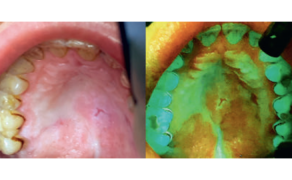

- W pracy omówiono przypadek leczenia wąskiej strefy dziąsła właściwego oraz cienkiego fenotypu dziąsłowego metodą przeszczepu nabłonkowo-łącznotkankowego.

Streszczenie: Liczne prace oryginalne i kazuistyczne pokazują wszechstronne zastosowanie terapii niskoenergetycznej LLLT (ang. low-level laser therapy) w stomatologii. Fotobiomodulacja laserowa istotnie poprawia efekty terapeutyczne zabiegów (działanie przeciwbólowe, przeciwzapalne i przeciwobrzękowe), zmniejsza ryzyko infekcji (działanie immunostymulujące), przyśpiesza procesy regeneracyjne w uszkodzonych tkankach (działanie biomodulacyjne), a tym samym zwiększa komfort życia pacjenta w fazie pooperacyjnej i/lub leczniczej. W pracy omówiono przypadek leczenia wąskiej strefy dziąsła właściwego oraz cienkiego fenotypu dziąsłowego metodą przeszczepu nabłonkowo-łącznotkankowego z podniebienia twardego dodatkowo wspomaganego LLLT.

Summary: Numerous original and casuistic papers show a comprehensive use of low-level laser therapy (LLLT) in dentistry. Laser photobiomodulation significantly improves the therapeutic effects of treatment (analgesic, anti-inflammatory and anti-swelling effects), reduces the risk of infection (immunostimulating effect), accelerates regenerative processes in damaged tissues (photobiomodulation effect), and thus increases the quality of life of a patient in the postoperative and/or therapeutic phase. The paper discusses a case of the treatment of the narrow gingiva and thin gingival phenotype using free gingival graft from the hard palate, additionally supported by LLLT.